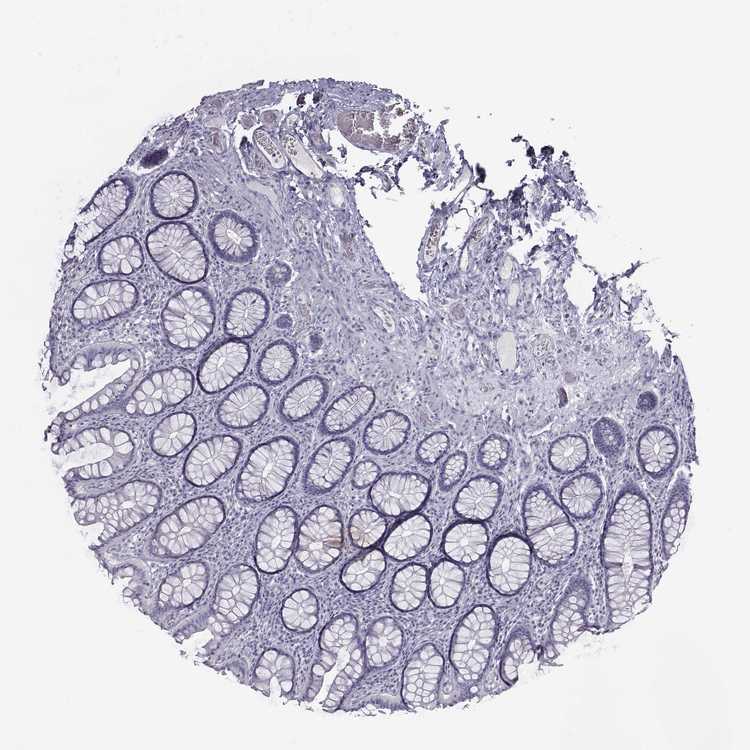

COLON - Antibody stainingi

Antibody staining in the annotated cell types in the current human tissue is reported as not detected, low, medium, or high, based on conventional immunohistochemistry profiling in selected tissues. This score is based on the combination of the staining intensity and fraction of stained cells.

Each image is clickable and will lead to virtual microscopy that enables deeper exploration of all samples and also displays staining intensity scores, fraction scores and subcellular localization as well as patient and tissue information for each sample.

Antibody HPA036263Antibody HPA041449

Endocrine cells Not detected-

Endothelial cells Not detectedNot detected

Enterocytes Not detected-

Enterocytes - Microvilli Not detected-

Fibroblasts Not detected-

Glandular cells -Not detected

Goblet cells Not detected-

Mucosal lymphoid cells Not detected-

Peripheral nerve/ganglion Not detectedNot detected